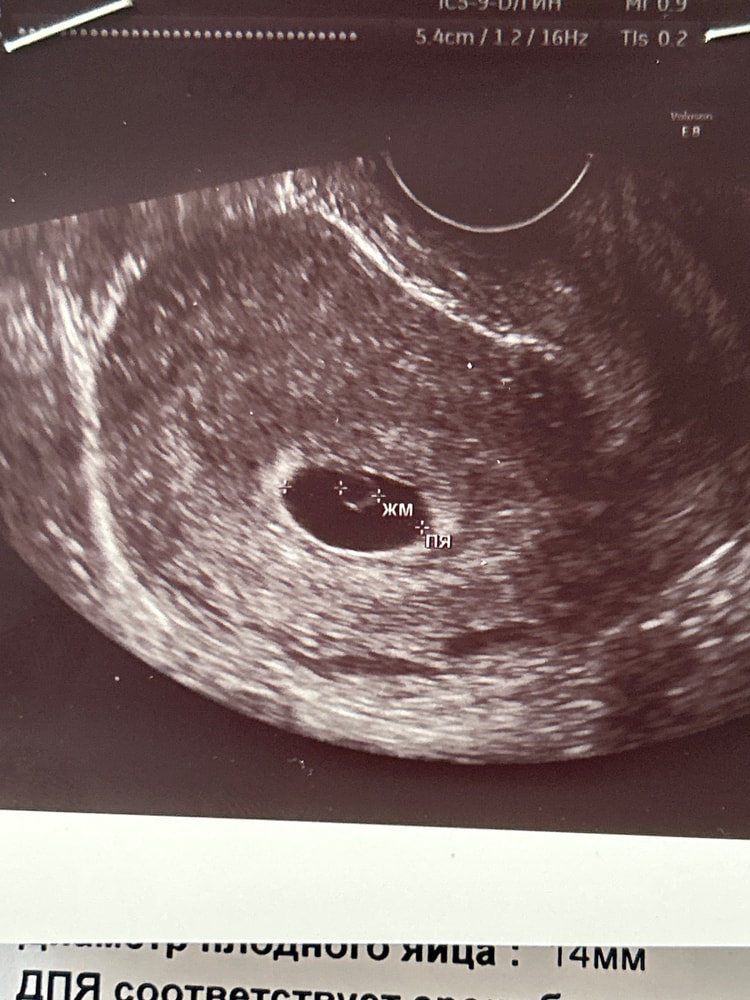

Всем привет! Возможно кто-то видел мой вопрос про узи в 4,4 недели (было ПЯ 4,3мм и больше ничего не увидели). Была вчера у другого УЗИста, срок по последним месячным 5+3. Увидели плодное яйцо 14 мм и ЖМ 4 мм, эмбриона нет. Есть у кого-то истории с похожими показателями и благоприятным исходом? Боюсь повторения аэмбрионии. Следующее узи будет на скоре 6,4

В 5,3 было плодное яйцо 10 мм, жм 3,5 мм, эмбриона не нашли, по узи срок поставили 4 недели. Сказали через пару недель повторить узи. Пришла в 7,4 уже все было хорошо эмбрион появился, даже сердцебиение у него определилось!

В 5,1 было только пя 8 мм и жм 1,6 через 9 дней в 6,3 акушерских пя 19,ктр 5,4 и ЧСС 146 уд/мин,рано ещё для эмбриона

Узи в 5,6 ПЯ 16 мм, жм 4 мм, эмбриона нет. Ровно через 10 дней срок 7,2 ПЯ 37 мм, КТР 10 мм, сб+